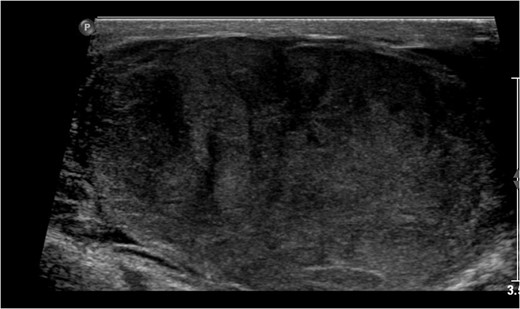

A 63-year-old gentleman who is a known case of dyslipidemia was presented to our Emergency Department with a right sided scrotal swelling and pain for 1 week. The patient had been having right testicular pain for the past 6 months on and off but never sought medical advice. On clinical examination, the patient had right scrotal swelling with epidydimal and cord tenderness and swelling, the cremasteric reflex could not have been assessed due to the large size of the scrotum with reactive scrotal wall edema. The patient underwent Doppler ultrasound which showed right testicular heterogeneous echotexture with nodular hypo-echoic areas (Fig. 1) with preserved vascularity. There was no evidence of testicular torsion or masses in that study. A provisional clinical correlation was made and the patient was diagnosed with right epididymo-orchitis and discharged home on oral antibiotics. Next day, the patient presented again to our ER with increased pain, swelling and erythema reaching the right inguinal area. So, the patient was admitted for administration of intravenous antibiotics. After 2 days of IV antibiotics, the patient’s condition was not improving which prompted the need of a CT scan. CT scan showed a heterogeneous enlarged right testis with twisting of the spermatic cord at the level of inguinal area and scrotal neck (Fig. 2). A diagnosis of testicular torsion was made based on these findings. The patient then underwent an urgent exploration with an inguinal incision which showed a hugely edematous cord, the incision was extended as Hockey-Stick incision and the right testis was delivered. The testis was dark, edematous, with no evidence of palpable testicular masses. The spermatic cord was twisted in 1080° clockwise fashion in three areas (Fig. 3). The first 360°, torsion was at the level of the deep inguinal ring, the second at inguinal part of the spermatic cord, and the third is just proximal to the testis. Right radical orchiectomy was carried out with high ligation of the spermatic cord at the level of deep inguinal ring, which was the site of normal, non-engorged cord. The procedure was completed with the extended inguinal incision with no violation of the scrotum, since the pathology was high in the inguinal area. The patient recovered very well with no complications.

Right testicular Doppler US showing hypo-echoic areas with heterogeneous echo-texture.

Neoplasms of the testis compromise a morphologically and clinically diverse group of tumors, of which more than 95% are germ cell tumors. Germ cell tumors are relatively rare accounting for 1–2% of cancers among men in the United States. Testicular cancer is the most common solid malignancy among men 20–40 years old. Seminoma is the most common type of germ cell tumors which occur at an older average age than non-seminoma germ cell tumors, with most cases being diagnosed between the fourth and fifth decade of life. The most common presentation of testicular cancer is a painless testicular mass, while acute testicular pain is less commonly seen [6]. Diagnostic delay is a very well recognized phenomenon in literature with previous studies reporting up to one third of testicular tumors were initially misdiagnosed as epididymitis or hydrocele [7]. Intra-scrotal testicular tumor torsion is extremely rare especially in old age [2]. To our knowledge only six cases in the English literature have been reported to date [Table 1]. In our case a testicular seminoma was overlooked initially due to multiple reasons. The seminoma has a non-specific ultrasound appearance as homogeneous hypo-echoic lesions [6]. In our case this could have had been masked by the following: the presence of a testicular heterogeneous echo-texture along with nodular hypoechoic regions in testicular ultrasound going more with chronic epididymo-orchitis when correlated with long standing history of the patient, false clinical examination as the testis could not have been palpated properly due to severe edema and congestion which could have masked the firm feeling of a seminoma; the presence of severely engorged spermatic cord with patent vascularity which makes engorgement of the testis and cord more of an inflammatory process rather than torsion or malignancy.